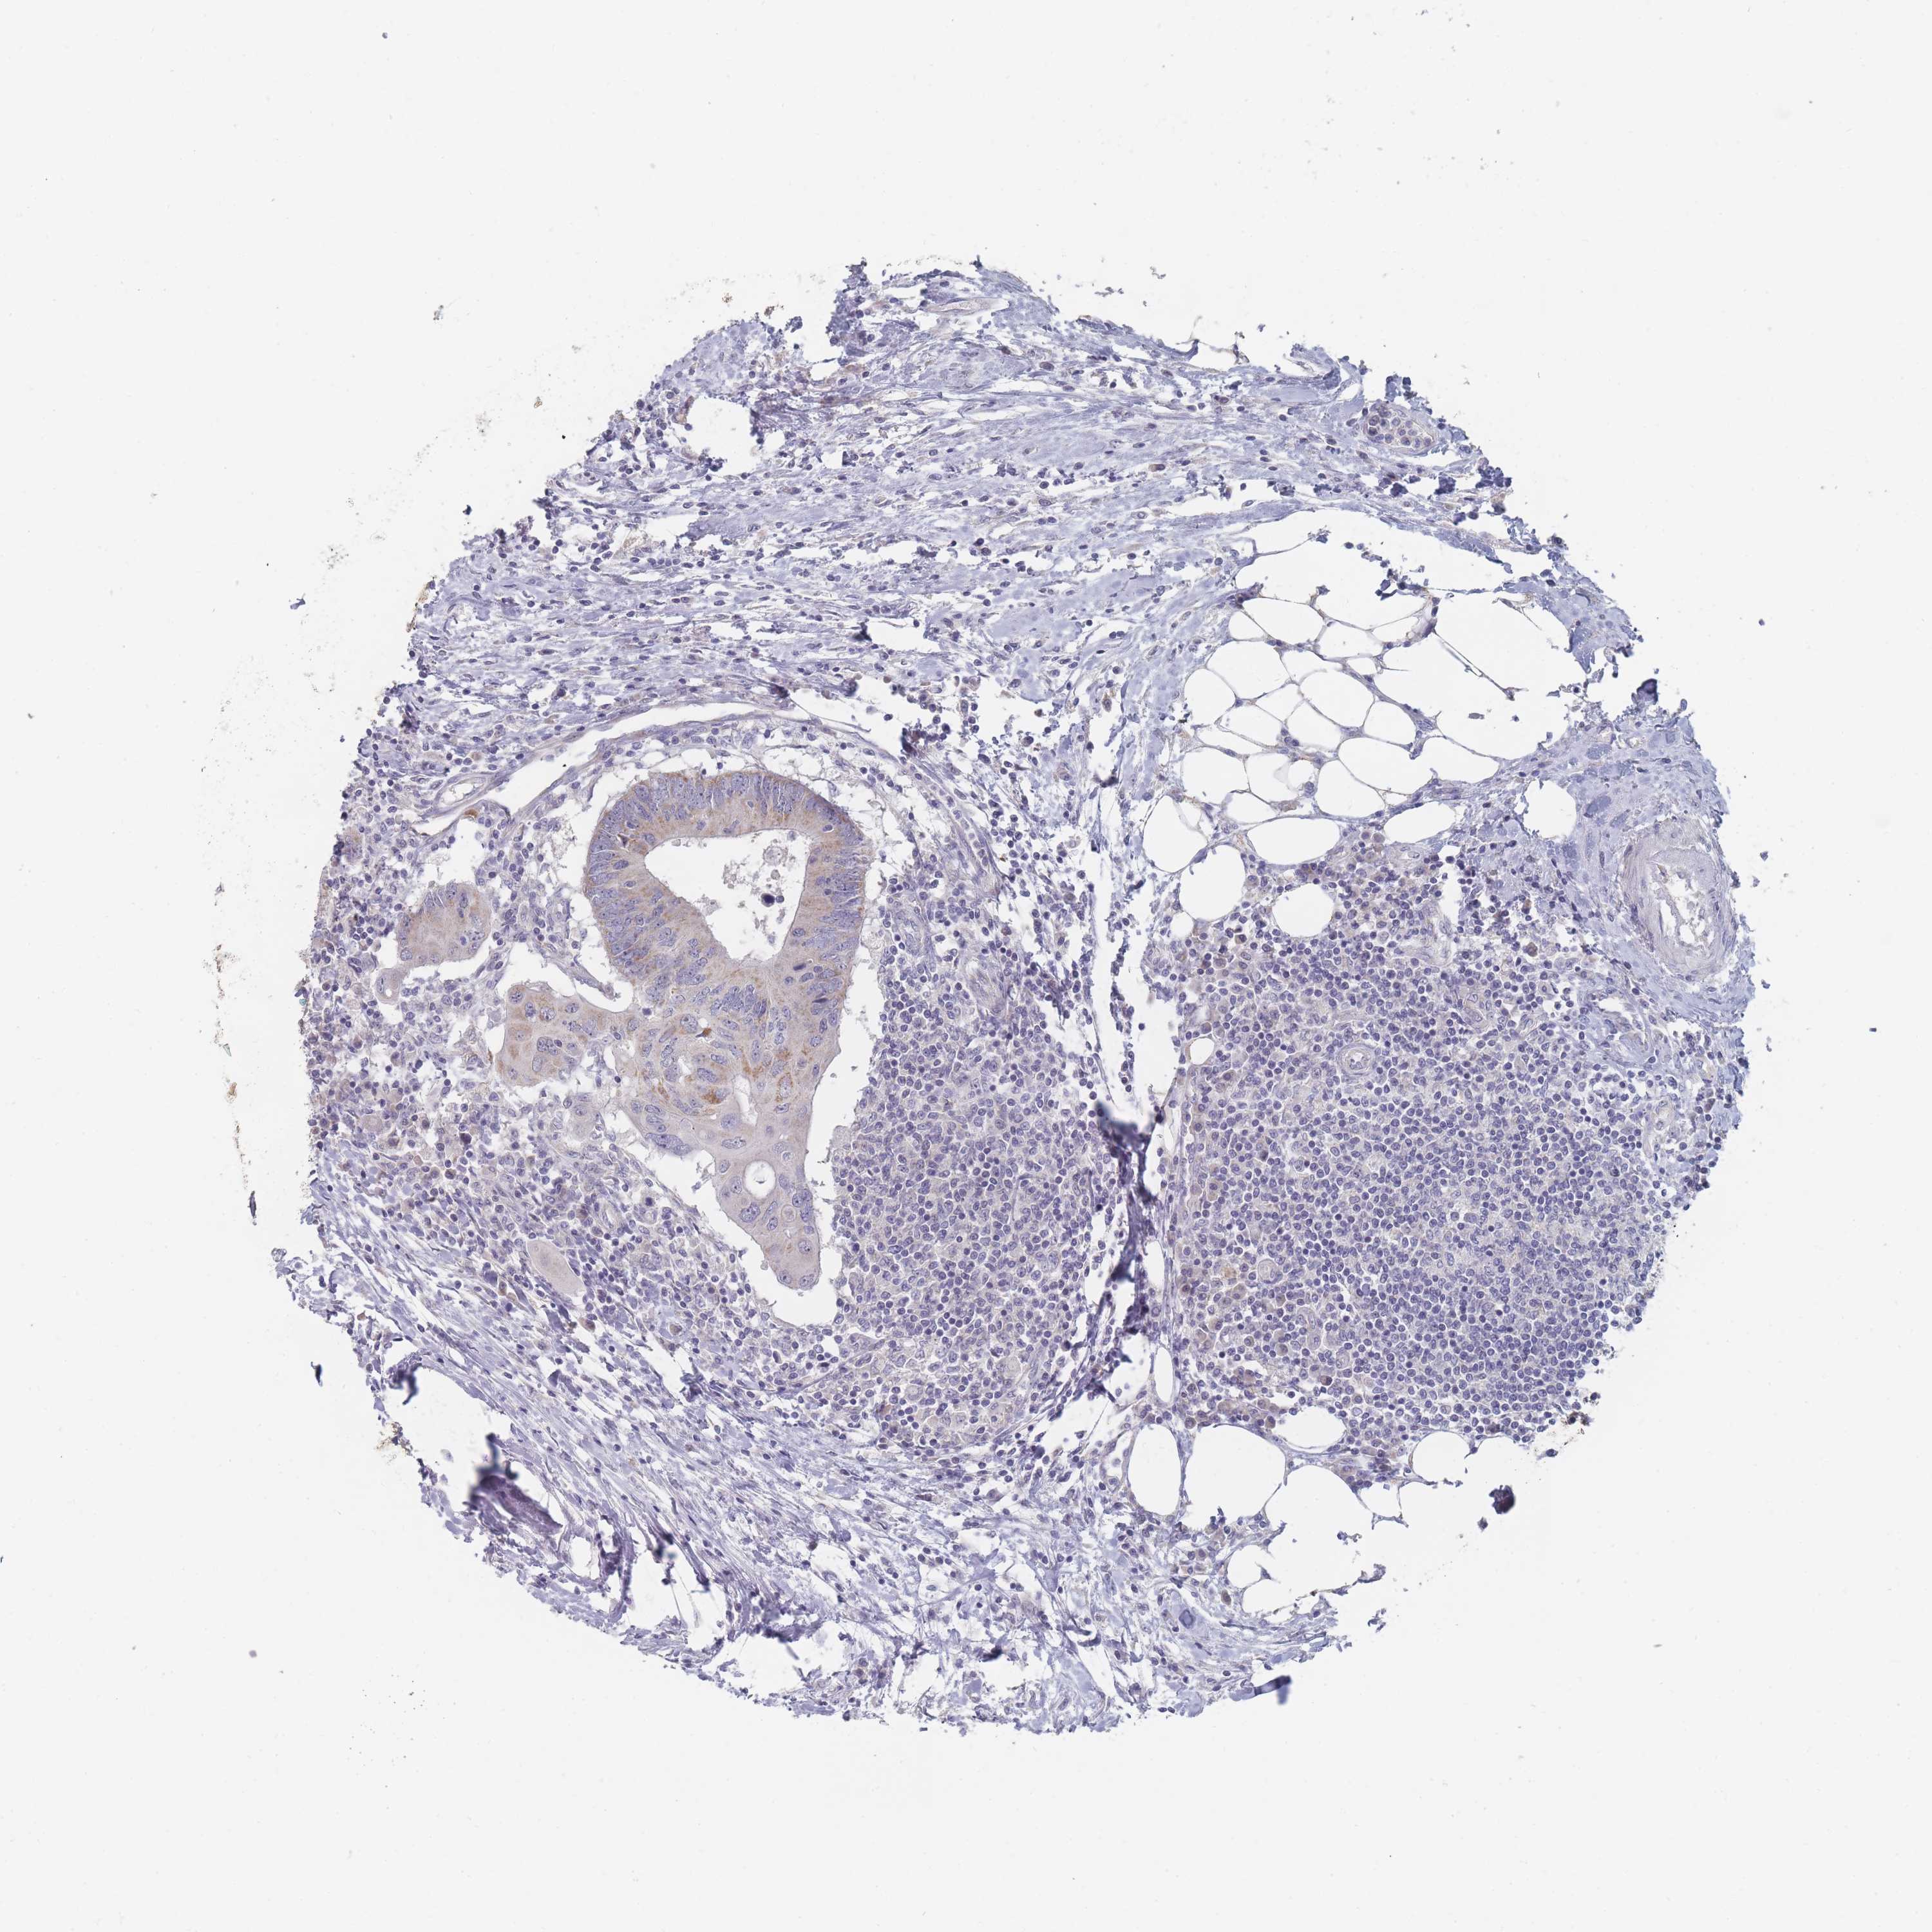

Colorectal cancer

Colon adenocarcinoma

Rectum adenocarcinoma